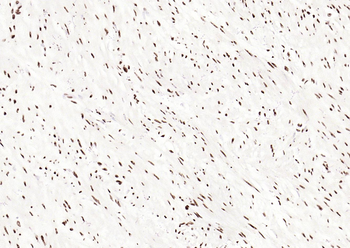

50 μl, 100 μlPhospho-Smad3 (Thr179) Rabbit Polyclonal Antibody [orb313112]

FC, ICC, IF, IHC-Fr, IHC-P

Bovine, Canine, Equine, Porcine, Sheep

Human, Mouse, Rat

Rabbit

Polyclonal

Unconjugated

100 μl, 200 μl, 50 μlSMAD7 Rabbit Polyclonal Antibody [orb500819]